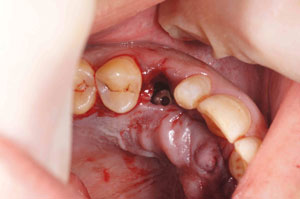

@A.Y.‚³‚ñ@31Î —«  ƒfƒUƒCƒi[@Žèp“ú@

‚Q‚O‚O‚W”N ‚TŒŽ‚P‚Q“úiŒŽj@‰ºŠ{

ƒm[ƒxƒ‹ƒKƒCƒhŽg—p

@@    ‰ºŠ{ ‚Q–{@”‚R‚UE”‚S‚U•”@’x‰„‰Ád

@   ”‚R‚U  Rpl Tapered Rp ‚SD‚Rmm ~ ‚P‚O mm@@@@”‚S‚U  Rpl Tapered Rp ‚SD‚Rmm ~ ‚P‚O mm